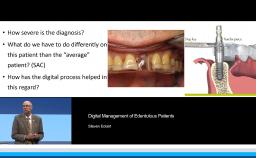

This lecture addresses role of digital imaging in restorative dentistry and discusses its use in facial, dentolabial, phonetic, and dental analysis. This presentation demonstrates the use of imported digital images, an iPad, and the free application iDraw for step-by-step facial analysis of a patient. The lecturer then demonstrates, the design of the smile line, first on the computer and then clinically. Transformation of 2D digital images to 3D images using the DSD Connect software is described. The lecture concludes with a clinical case carried out digitally from start to finish using intraoral scans and CBCT for implant planning and guided surgery.

apply digital imaging in restorative dental practice using available software applications